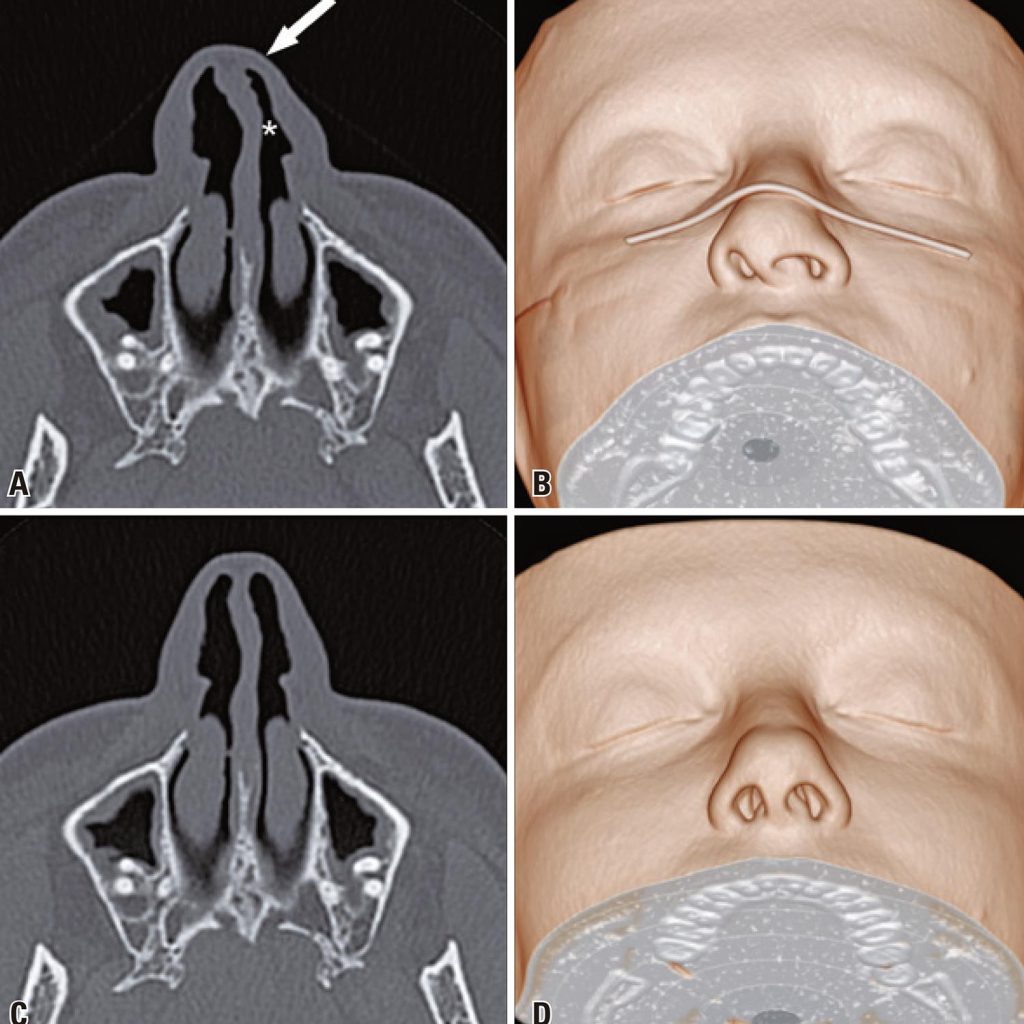

The widespread use of face masks is an essential tool for slowing the spread of the coronavirus disease 2019 pandemic and its adoption is recommended by the World Health Organization (WHO).() During the pandemic, several computed tomography scans of patients wearing face masks showed prominent nasal deformation, such as nasal septal deviations and nasal airway narrowing, which were absent in examinations of the same patients performed before the pandemic (). Therefore, care should be taken when evaluating the imaging examinations of the nasal region of patients wearing face masks.